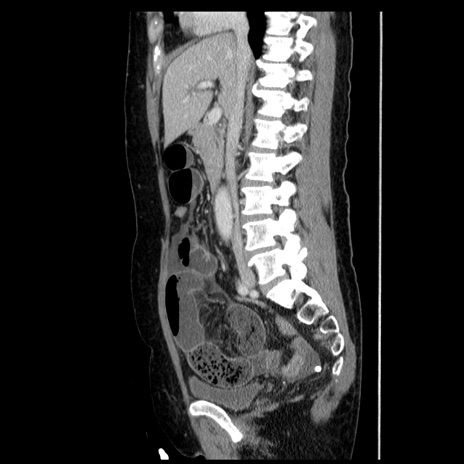

症例6(矢状断像)

【症例】50歳代女性

【主訴】下腹部痛

【現病歴】本日朝より下痢2回あり。 昼食を食べた後、嘔吐3回、下腹部痛認め、症状軽快せず、当院救急搬送。

最終食事:本日昼(生ものなし)。 昨日の夜、刺身を食ぺたとのこと。周囲に同様の症状の者なし。普段、排便は毎日あるとのこと。

【既往歴】卵巣癌術後(8年前に当院で卵巣摘出)

【身体所見】 意識清明、腹部:平坦、腸蠕動音→、やや硬、下腹部自発痛・圧痛あり、反跳痛あり、筋性防御なし。

【データ】WBC 16000、CRP 0.01